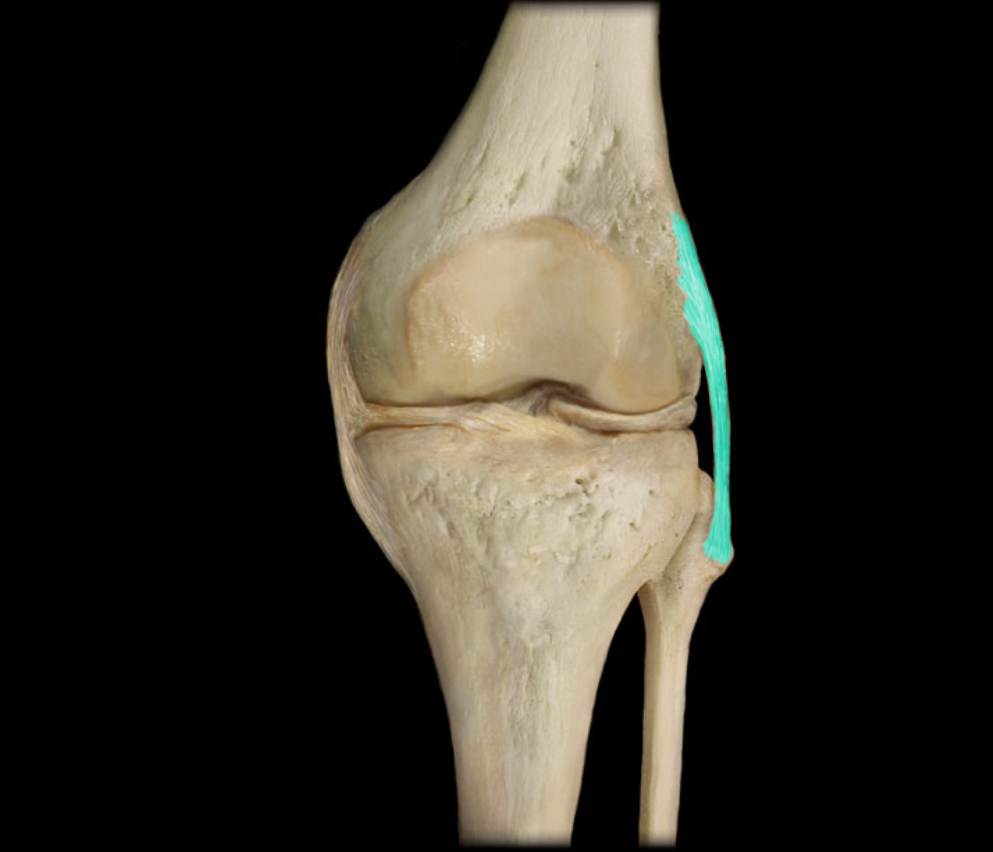

Fibular collateral ligament

Tibial collateral ligament